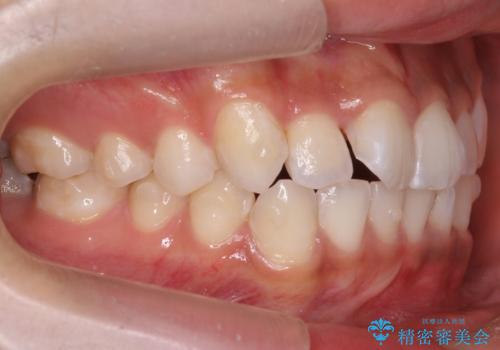

前歯のがたつき 1年かからず治療 マウスピース矯正

- 前歯のがたつきを主訴に来院。

インビザラインで歯を抜かずに並べました。

マウスピースの延長(リファインメント)もなく、短期間で綺麗に並びました。